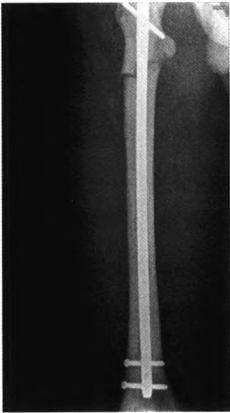

图4.后右股骨正位X线片示髓内钉长度及位置适宜

患者人院后给予消肿、镇痛、改善微循环等对症治疗,行骨牵引纠正骨折畸形。排除手术禁忌证后在腰硬联合麻醉下行右股骨骨折切开复位髓内钉内固定术。患者取平卧位,采用右大腿近端前外侧人路,显露骨折断端,探查见股骨转子下横行骨折,股骨近端髓腔相对较窄,骨质致密坚硬,多为硬化增厚的皮质骨,断端坎顿少量碎骨片及软组织,清理骨折断端,继而自切口内向近端逆行开口扩髓,再从股骨大转子自近端做纵行切口6 cm,依次切开皮肤皮下及阔筋膜张肌,自梨状窝开口处放人导针,借复位钳及牵引骨折复位后将导针插入股骨远端,近端扩髓至13 mm,远端扩髓至11mm,测量无误后放置lO mm*360 mm股骨顺行髓内钉,在C臂机透视下应用瞄准器锁人2枚远端锁钉,回敲加压断端,近端锁入1枚锁钉。手术历时2.5 h,术中出血量约250mL。定期复查股骨正侧位x线片,监测骨折愈合情况及石骨症病情进展情况(见图3~4)。

石骨症多无特异性的临床表现,多因外伤后骨折就诊,目前对于石骨症的确诊多依靠影像学检查。X线片中常见的有全身骨密度普遍增高、颅底硬化明显,椎体呈“夹心蛋糕样”特征性改变,两侧髂骨翼呈典型“同心环状征”,肋骨可呈“串珠样”改变等等。本例患者因跌倒后就诊,肢体外观并无异常性改变,诊断也主要靠影像学的特征性表现。成人石骨症合并骨折多可手术治疗,国内报道的数篇关于石骨症合并股骨近端骨折的手术方式多为锁定钢板固定及髓内固定。考虑因石骨症骨质致密且内部血管网稀疏,髓腔过于狭窄,扩髓钻孔的方式难以实现且可能发生医源性的再骨折,但此患者骨皮质硬化出现了少见的不对称性,右股骨骨皮质明显低于左侧,相对更易于实现扩髓操作,故此患者采用髓内固定的手术方式,从X线片和术中探查见右股骨远端骨皮质较近端逐渐增厚,不需阻挡钉辅助固定尾端。术后复查X线见内固定装置位置可,下肢力线良好,内固定装置无松动。